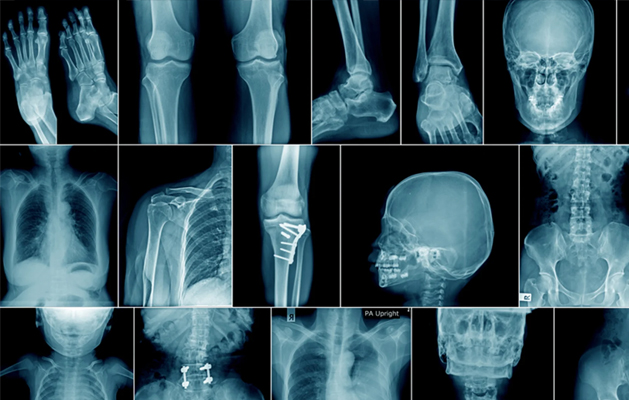

Best Clinical X-RAY in Chennai

Making the transition from analog to digital could bring several advantages to X-Ray Imaging. These would include improvement in contrast and other aspects of image quality by means of image processing Digitally Computed Radiography (DR) systems use equipment similar to conventional radiography except that in place of an X-Ray film, an imaging plate is used to create the digital image, which is then transferred to a computer using digital transfer method. X-Ray films are no longer taken to a darkroom or an automatic film processor to be developed in chemical tanks but With Computed Radiography, the imaging plate transfers digitally to the computer to appear on the screen. the digital image can then be viewed and be contrasted or colour-enhanced for better visibility. Digital Images can be documented on CD’S or printed on high-quality paper or simple viewed on a computer monitor.

X-rays are commonly produced by accelerating (or decelerating) charged particles; examples include a beam of electrons striking a metal plate in an X-ray tube and a circulating beam of electrons in a synchrotron particle accelerator or storage ring. In addition, highly excited atoms can emit X-rays with discrete wavelengths characteristic of the energy level spacings in the atoms. The X-ray region of the electromagnetic spectrum falls far outside the range of visible wavelengths. However, the passage of X-rays through materials, including biological tissue, can be recorded with photographic films and other detectors. The analysis of X-ray images of the body is an extremely valuable medical diagnostic tool.

X-rays are a form of ionizing radiation—when interacting with matter, they are energetic enough to cause neutral atoms to eject electrons. Through this ionization process the energy of the X-rays is deposited in the matter. When passing through living tissue, X-rays can cause harmful biochemical changes in genes, chromosomes, and other cell components. The biological effects of ionizing radiation, which are complex and highly dependent on the length and intensity of exposure, are still under active study (see radiation injury). X-ray radiation therapies take advantage of these effects to combat the growth of malignant tumours.